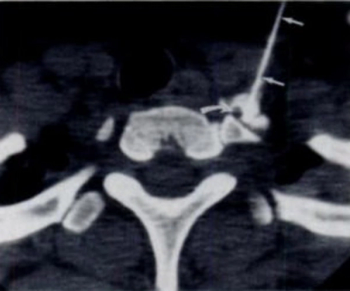

Utilizing computed tomography (CT) guidance, researchers have found that performing a minimally invasive anesthetic injection into the stellate ganglia may help address parosmia due to COVID-19, according to study results that will be presented at the annual Radiological Society of North America (RSNA) conference next week.